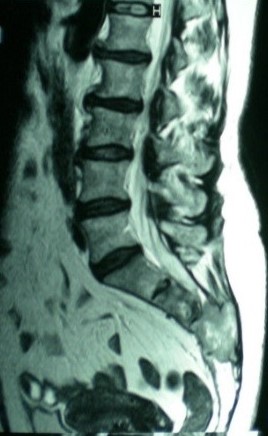

Sacrectomía parcial por abordaje posterior único. [Partial sacrectomy by single posterior approach.]